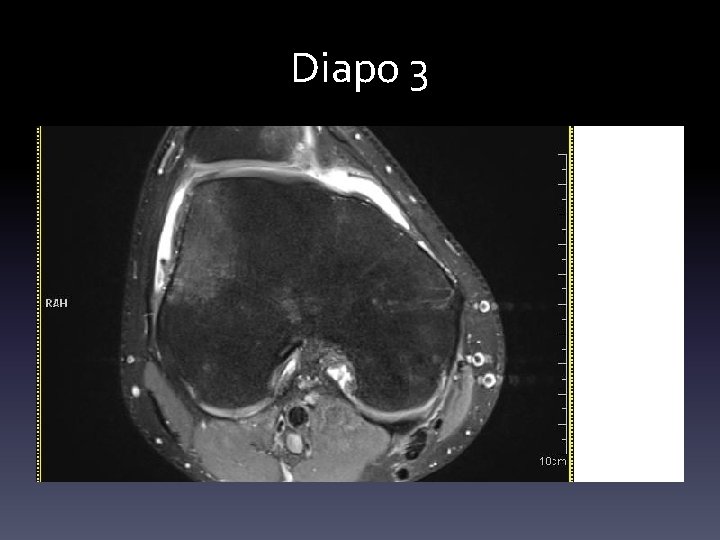

RADIOLOGIE • Le diagnostic est évident avec une rotule latéralisée (diapo 1) • Il l’est moins en cas de luxation auto réduite (diapo 2) • On rechera une trochlée plate, une rotule haute, on précisera le mécanisme de l’accident etc… • Si une irm est réalisée: on voit une contusion osseuse du bord latéral du condyle , et/ou une rupture du ligament fémoropatellaire médian( diapo 3)

Diapo 3